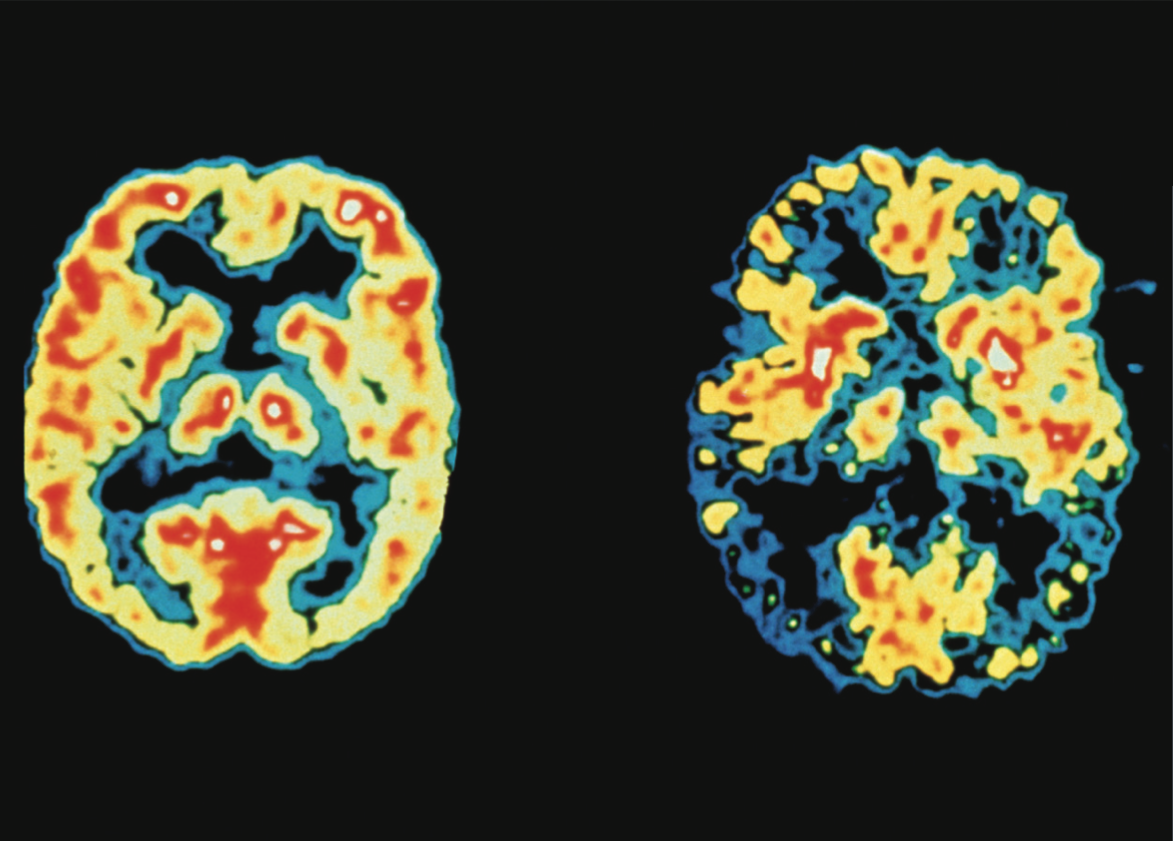

Alzheimer-Erkrankung

Vaskuläre Demenz